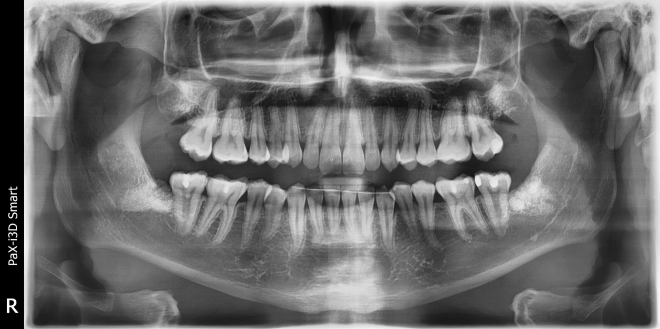

• Діагностика. 6 діагнозів.

• Класифікації за рівнем складності

• Техніки видалення зубів особливості планування від розрізу до останнього шва